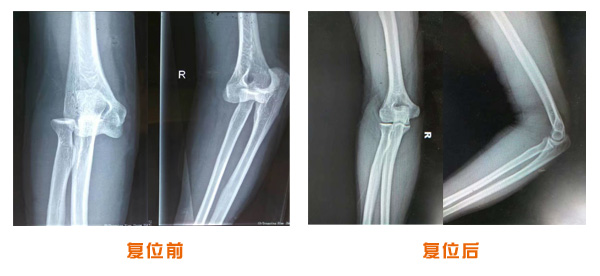

肥城市安駕莊梁氏骨科醫(yī)院是一所以梁氏手法正骨配合膏藥為特色的現(xiàn)代化??漆t(yī)院。

梁氏骨科術(shù)始創(chuàng)于清雍正年間,歷經(jīng)八代,至今已有三百年歷史。據(jù)1929年泰安縣志載“梁瑞圖先生,字增生,號(hào)蓮峰,安駕莊人,精岐黃并發(fā)明接骨,凡跌打車凡跌打車軋皮不破而碎骨者......【詳細(xì)】 |